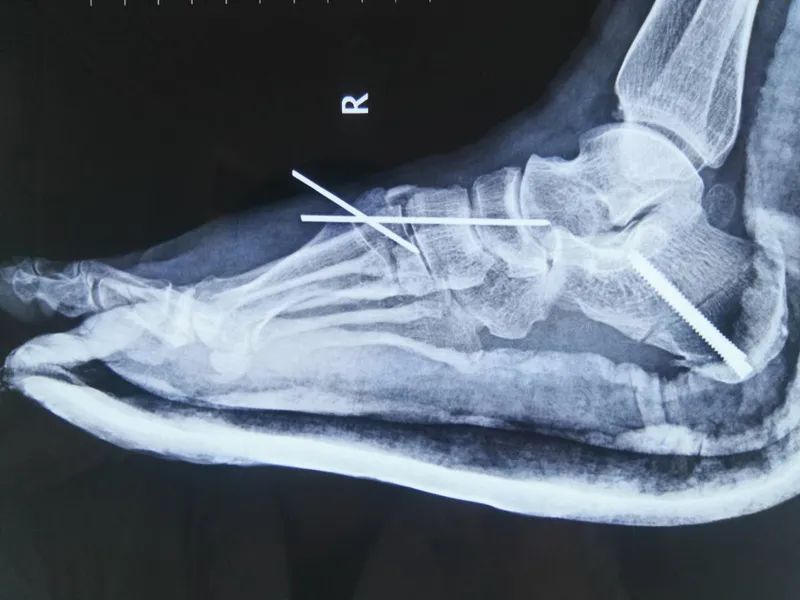

术前无明显足弓

术后足弓恢复

据了解,该手术通过五个切口,六种术式进行,根据王女士的病情将她脚上的畸形骨头进行矫正固定,手术过程难度很大,包括了两个四级术式以及四个三级术式,其中跟骨截骨术、跗骨成形术为四级手术,并且是巴彦淖尔市医院手足显微外科的新技术项目,四个三级手术包括副舟骨切除、腓肠肌松解、胫后肌重建、髂骨取骨植骨术。扁平足和高弓足标准截骨的手术治疗是足踝治疗成熟的标志,该手术的顺利实施标志着巴彦淖尔市医院手足显微外科在足踝治疗领域已发展成熟。

目前,王女士的足弓恢复了,力线得到纠正,足踝部疼痛基本消失,经过一段时间的康复训练,走路也将恢复正常。